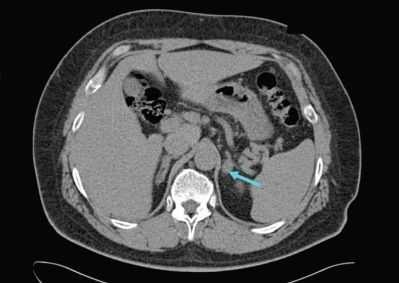

УЗИ надпочечников — низкочувствительный метод диагностики. Предпочтительнее проводить КТ: она помогает выявить как макро- и микроаденомы надпочечников, так и утолщения ножек надпочечников, гиперплазии и другие изменения [14] .

![Аденома левого надпочечника]()